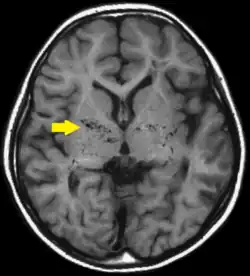

T1-weighted MR image of moyamoya disease. Flow void in the basal ganglia is indicated by the arrow.